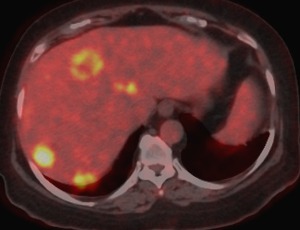

Comparative evaluation of diffusion-weighted MRI and 18F-FDG PET-CT for detection and volumetric assessment of colorectal cancer liver metastases

Purpose: To compare diffusion-weighted imaging (DWI) and 18F-FDG PET-CT for detection and volumetric assessment of colorectal cancer liver metastases, evaluating the optimal b-value for volumetric correlation with metabolic tumor volume (MTV).

Materials and Methods: This retrospective study included 50 patients with histopathologically confirmed colorectal adenocarcinoma and liver metastases who underwent both PET-CT and liver MRI (including DWI at b=50, 400, 800 s/mm²) within 30 days. Synthetic DWI images at b=1000, 1500, and 2000 s/mm² were generated.